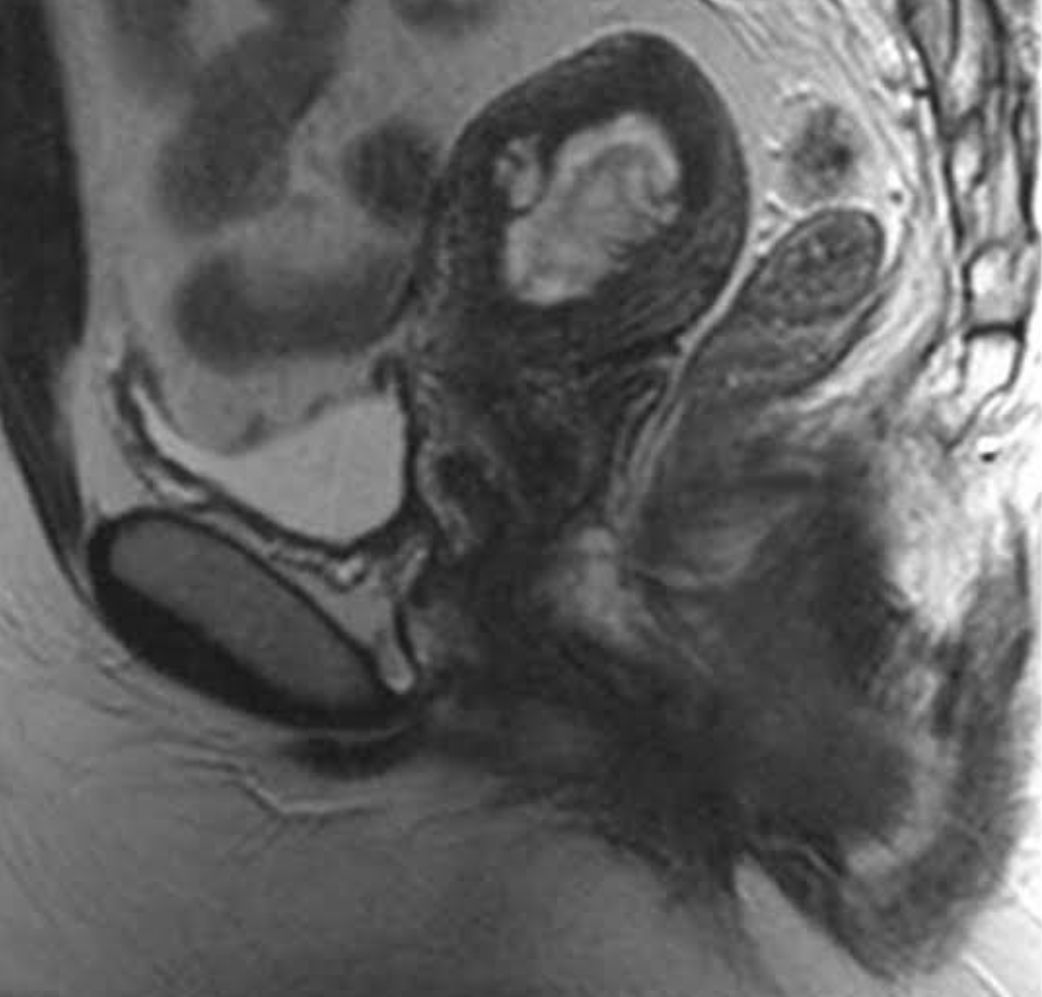

เมื่อคุณทำอัลตราซาวนด์หรือ MRI เยื่อบุโพรงมดลูกของคุณจะปรากฏเป็นเส้นสีเข้มบนหน้าจอ บางครั้งเส้นนี้เรียกว่า "แถบเยื่อบุโพรงมดลูก" คำนี้ไม่ได้หมายถึงภาวะสุขภาพหรือการวินิจฉัยโรค แต่หมายถึงเนื้อเยื่อปกติของร่างกาย

ในการตั้งครรภ์ตามปกติ แถบเยื่อบุโพรงมดลูกจะกลายเป็นที่อยู่ของทารกในครรภ์ที่กำลังเจริญเติบโต แถบนี้จะถูกบดบังด้วยถุงตั้งครรภ์และรก